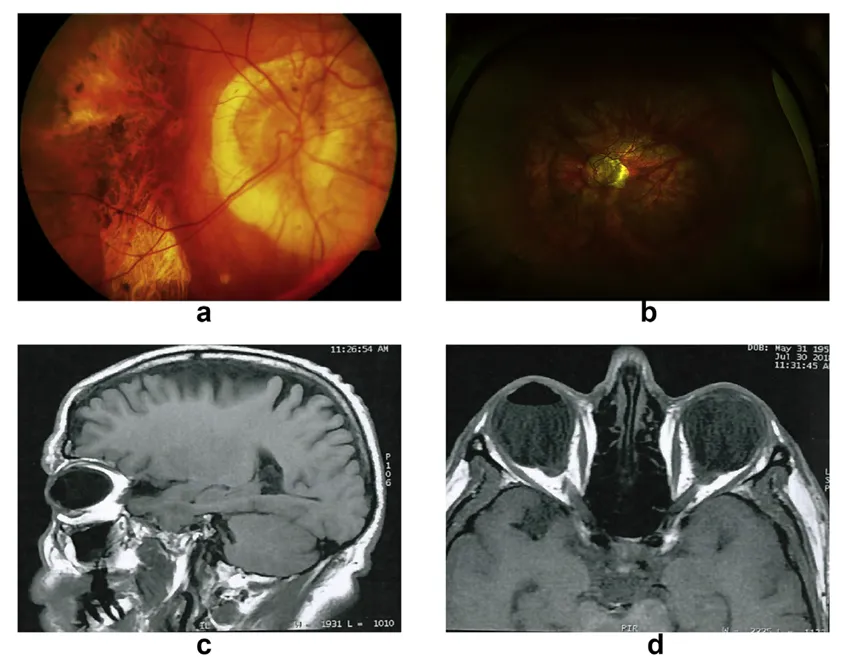

圖3:同一近視患者右眼(a,b)與左眼(c,d)的影像。注意左眼(cd)中圍繞中心已癒合的近視性脈絡膜新生血管周圍萎縮區域的進展情況

圖圖6:高度近視眼中顯著的視網膜色素上皮及脈絡膜視網膜萎縮伴隨垂直型後葡萄腫(圖a)。 34歲高度近視患者,鞏膜扣帶術後出現後葡萄腫(圖b)。無晶體高度近視患者左眼視網膜剝離術後磁振造影,顯示前房內氣體及後葡萄腫(圖c、d)